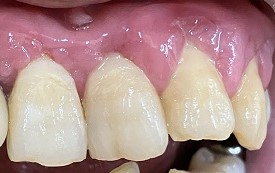

下画像3

重度歯周病 強い歯肉の腫れ